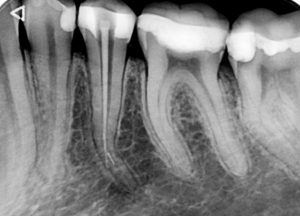

Случай на релечение на долен пети зъб, в който предишният колега беше фрактурирал канален инструмент и в опита си да довърши

лечението бе перфорирал и корена на нивото на извивката.

Освен перфорацията, извивката и счупения канален инструмент,

сложността на случая идваше и от факта, че коренът беше изключително тесен в областта на

извивката и имаше голяма опасност при

премахването на инструмента зъбът допълнително да се отслаби на

това място.

След изключително щадящо премахване на инструмента,

каналът бе обработен до невероятните 27 мм.

След което, заедно с перфорацията, беше запълнен с

биокерамичен сийлър